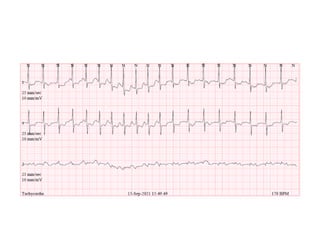

This document appears to be a medical record discussing Holter monitoring. It mentions reading and interpreting Holter data and includes the name of a doctor, date, and some medical abbreviations. However, there is not enough contextual information to provide a more detailed summary.